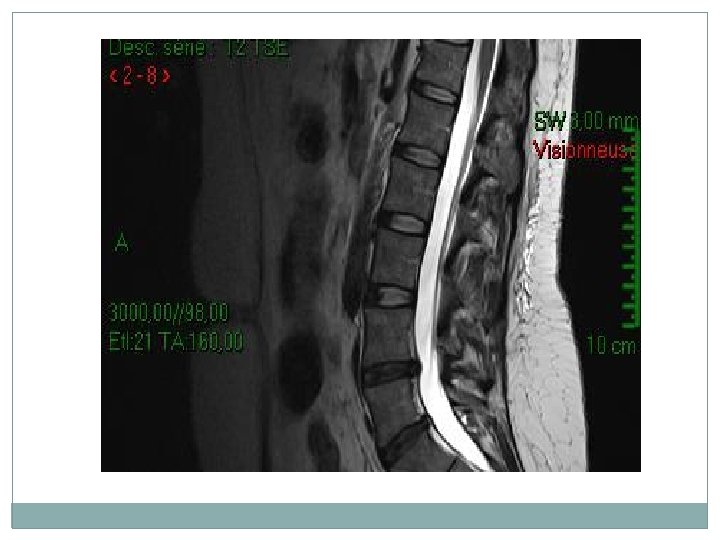

L’imagerie par résonance magnétique (IRM) lombosacrée �L'analyse des migrations herniaires et des sténoses canalaires associées. • L'exploration d'emblée de 1'ensemble des disques lombaires grâce aux coupes sagittales. • L'exploration du compartiment intradural.